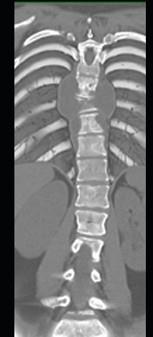

问题 男,34岁,发热,背部疼痛,不能直立,局部软组织肿胀,结合图像,最可能的诊断是 ( )

选项 A、骨肉瘤 B、成骨肉瘤 C、脊柱结核 D、脊柱转移瘤 E、化脓性骨髓炎

答案 E